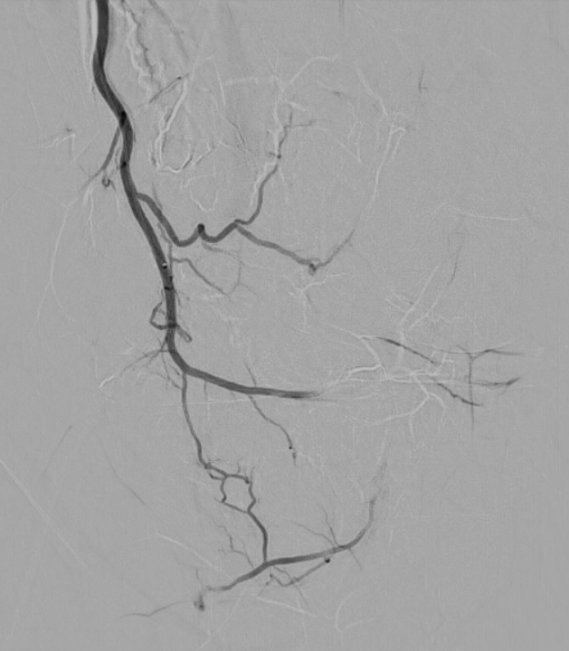

Letztlich sind alle diese längerfristig bestehenden Schmerzen durch eine chronische Entzündung bedingt. Dies ist keine bakterielle Entzündung, sondern eine "normale" Reaktion des Körpers. Es kommt zum Einsprossen von neuen, kleinen Blutgefäßen und neuen Nervenbahnen, welche die Schmerzen weiterleiten können.

Diese neuen, kleinen Blutgefäße sind der Angriffspunkt dieser innovativen Schmerztherapie. Durch dieses minimalinvasive Therapieverfahren erfahren Sie eine umgehende und lang anhaltende Schmerzlinderung.

Die Schmerzbehandlung durch transarterielle Mikroembolisation (TAME) ist eine innovative medizinische Behandlungsmethode, welche sich in den letzten Jahren stark verbreitet hat. TAME hat sich als effektive Option in der Schmerztherapie etabliert, da sie nicht nur die Lebensqualität der Patienten verbessert, sondern auch in vielen Fällen die Notwendigkeit von Schmerzmitteln verringert. Informieren Sie sich selbst - für Kritik, Anmerkungen oder Fragen stehe ich gerne zur Verfügung!